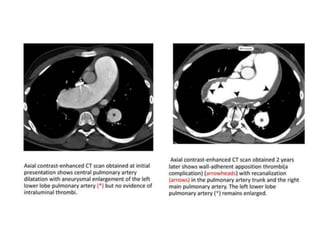

Pulmonary Artery Hypertension

 Findings in CT:

• Extra cardiac vascular signs:

• Enlarged pulmonary trunk >29 mm diameter is often

used as a general predictive cut-off

• Enlarged pulmonary arteries

• Mural calcification in central pulmonary arteries

• Evidence of previous pulmonary emboli

• Cardiac signs:

• Right ventricular hypertrophy: defined as wall

thickness of more than 4 mm.

• Straightening or bowing (towards the left ventricle)

of the interventricular septum

• Right ventricular dilatation

• Decreased right ventricular ejection fraction

• Dilatation of the inferior vena cava and hepatic veins

• Pericardial effusion

• Parenchymal signs:

• Centrilobular ground-glass nodules (Cholesterol

granuloma).

• Neovascularity: tiny serpiginous intrapulmonary

vessels that often emerge from centrilobular

arterioles.